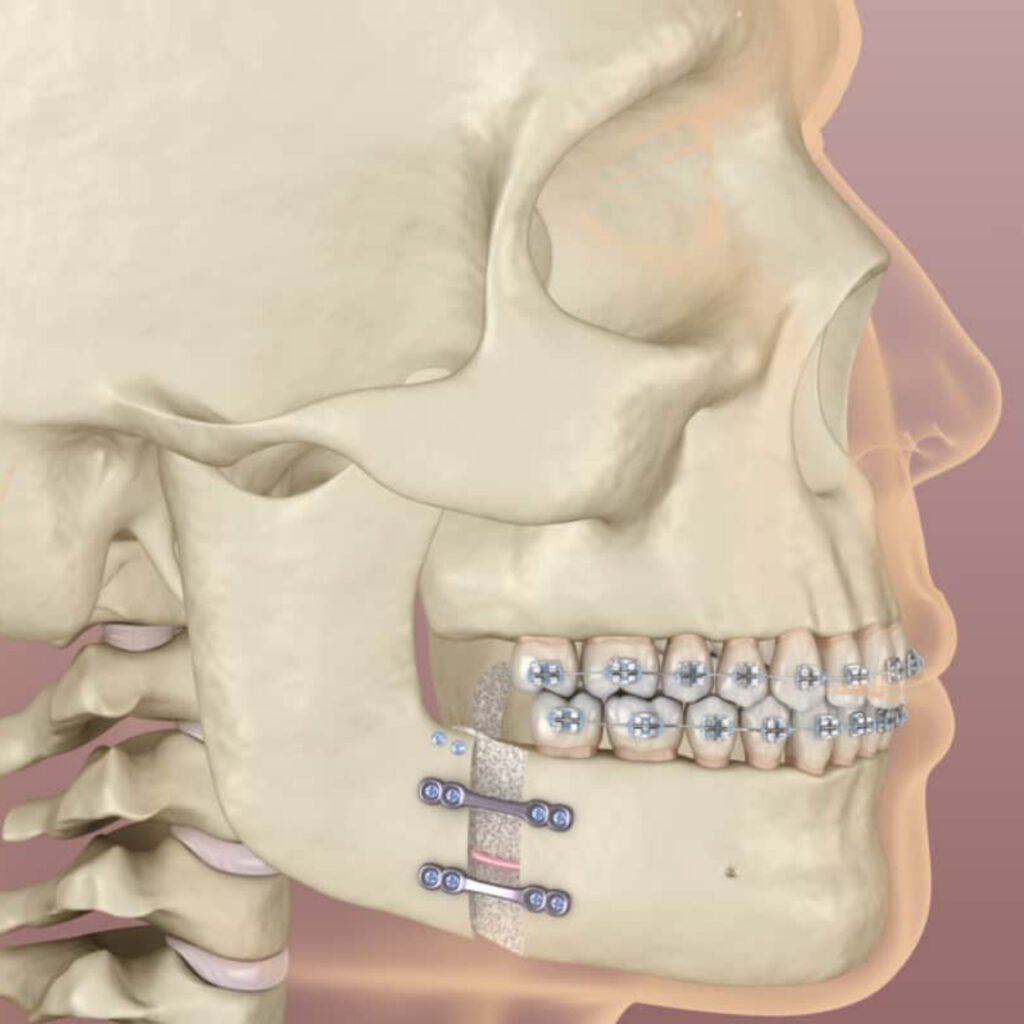

Whether it’s an issue with jaw alignment, facial asymmetry, bite correction, or trauma-related reconstruction, our surgical interventions are carefully planned and executed to restore both function and facial aesthetics. Jaw surgery (orthognathic surgery) not only improves chewing, speech, and breathing but also enhances the overall appearance of the face.

We use modern diagnostic tools, 3D imaging, and precision surgical techniques to deliver results that are safe, effective, and lasting.